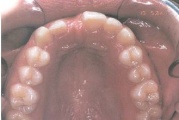

Ülemise hambakaare kitsenemine ehk tagumiste hammaste risthambumus.

Suulaepoolt lõikunud koonilise kujuga lisahammas